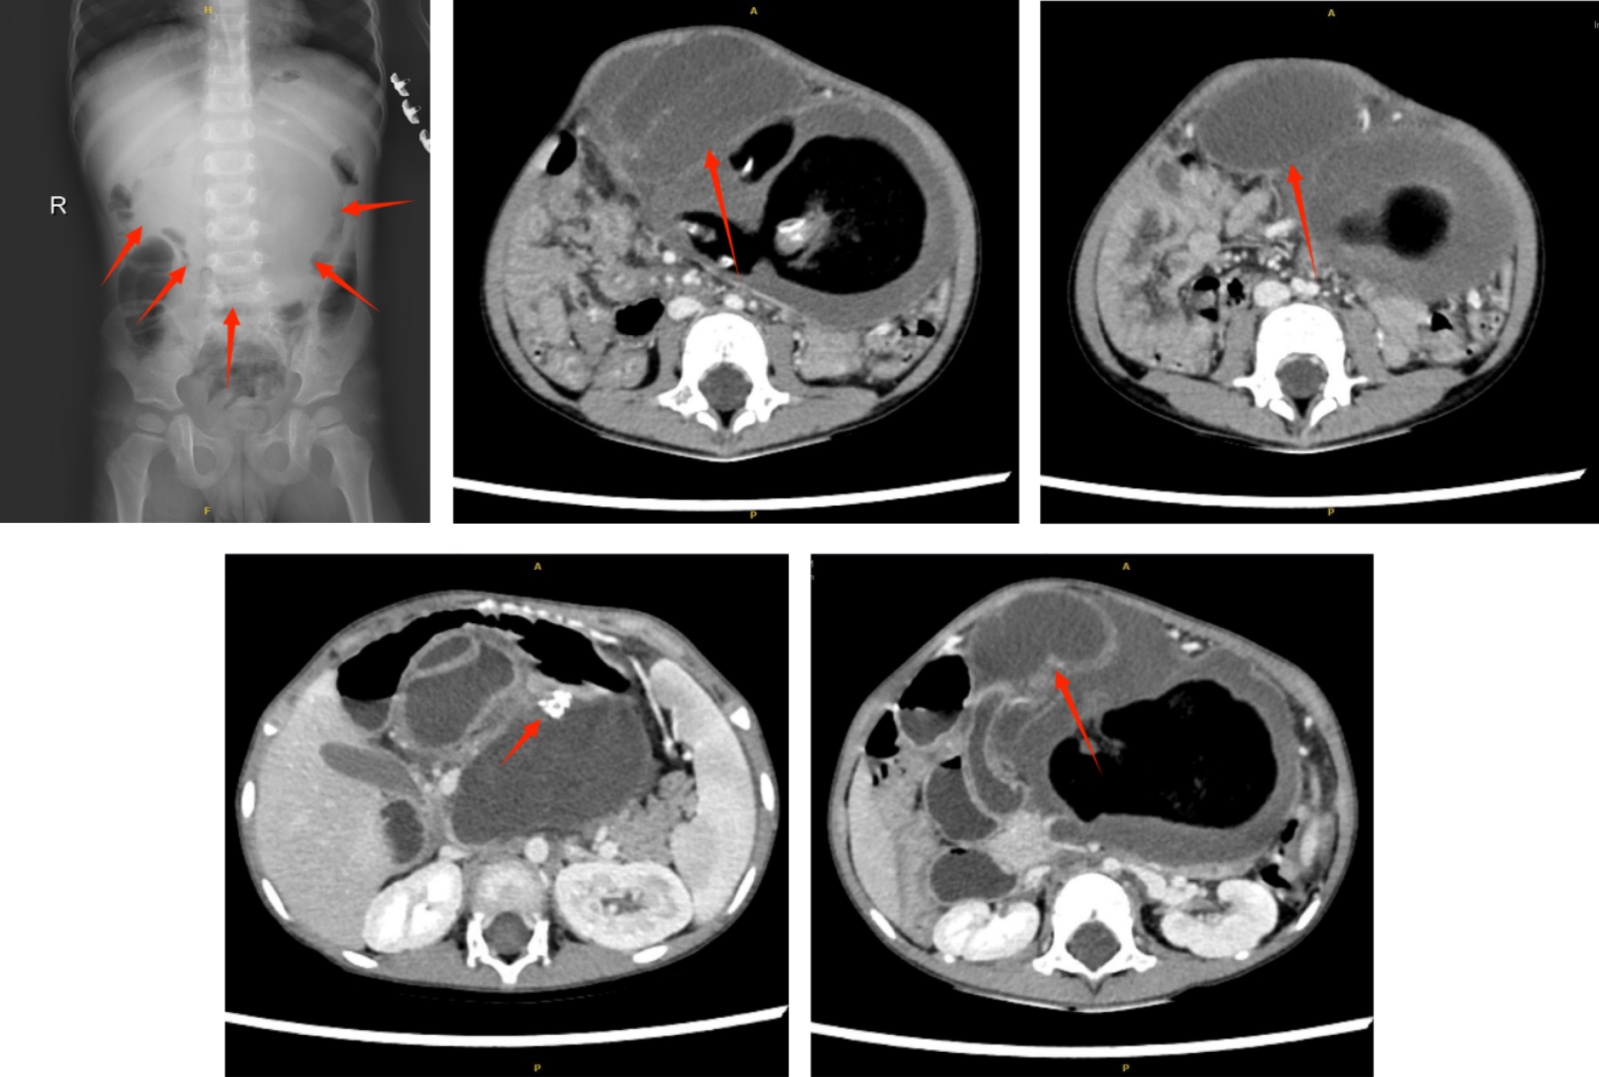

Figure 2. Preoperative abdominal upright plain film and enhanced CT images of the child

2. 患儿术前腹部立位平片及增强CT图像

然而,患儿的确诊有赖于入院后的进一步检查,盆腔CT显示腹腔偏左侧见巨大团块状混杂密度灶,脂肪密度影、软组织密度及骨性密度影(图2),周围可见囊性低密度,病灶边缘可见多发迂曲扩张肠管影,可见系膜影,邻近结构受推压,最大径约10.6 cm,右上腹见扩张肠管,内见积液;胰腺受压,大部分显示欠清,胰尾部显示可,未见异常密度,胰管未见明显扩张。增强CT:增强扫描可见系膜血管影,与病变内部结构相连。经过CT提示:腹腔内巨大占位,考虑为腹腔内寄生胎,术前实验室检查:NSE:28.3 ng/ml↑;CA19-9:107.00 U/ml↑;CA125:75.70 U/ml↑;CA153:10.40 U/ml;CEA:29.10 ng/ml↑;AFP:<0.91 ng/ml (图3)。初步明确肿物的性质后,我们为患儿实施了开放手术并完整切除了肿物,手术中:见肿物为腹膜后来源,大小约15*9*8 cm,右侧为囊性部分,左侧为囊实性部分,与胰腺及脾静脉关系密切,胰腺被挤压向前下,质地菲薄。肿瘤巨大,自腹部刀口显露困难,自右侧抽取囊液共约400 ml,为白色浑浊粘稠液体。打开后腹膜,沿肿瘤边缘锐、钝性分离,逐渐将肿瘤完整切除,见后腹壁正中有一肿瘤的主要供血血管。标本术后给予剖开,见右侧为肠管组织,内有肠液、脓液样物质及肠粘膜组织,左侧内有大量皮脂样物质、脂肪组织及软骨组织,标本家属过目后送常规病理。病理(图4):病理查见皮肤、皮下组织、胰腺组织、神经组织、骨、软骨及骨髓组织,局部见完整的肠壁、胃壁结构及衬覆尿路上皮的管状结构,结合临床及影像学检查,最终诊断为寄生胎。